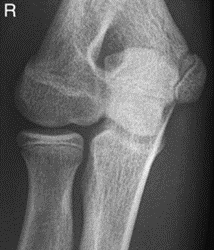

Które zdjęcie RTG stawu łokciowego zostało wykonane w projekcji skośnej w rotacji zewnętrznej?

A. Zdjęcie 1

B. Zdjęcie 2

C. Zdjęcie 3

D. Zdjęcie 4